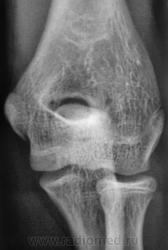

Травма. Пациент направлен на рентгенографию локтевого сустава.

Ну сломал локтевой отросток-с кем не бывает.

А мне не очень нравится головка и шейка луча.

а внутренний надмыщелок?

Надмыщелок, кажется, действительно отломан. А вот других повреждений не вижу.

Мы не знаем возраста пациента.Судя по зонам роста-молодой.По поводу надмыщелка-см.И.Королюка.

А. как быть с прерывистостью контура?

Там проходит ростковая зона.